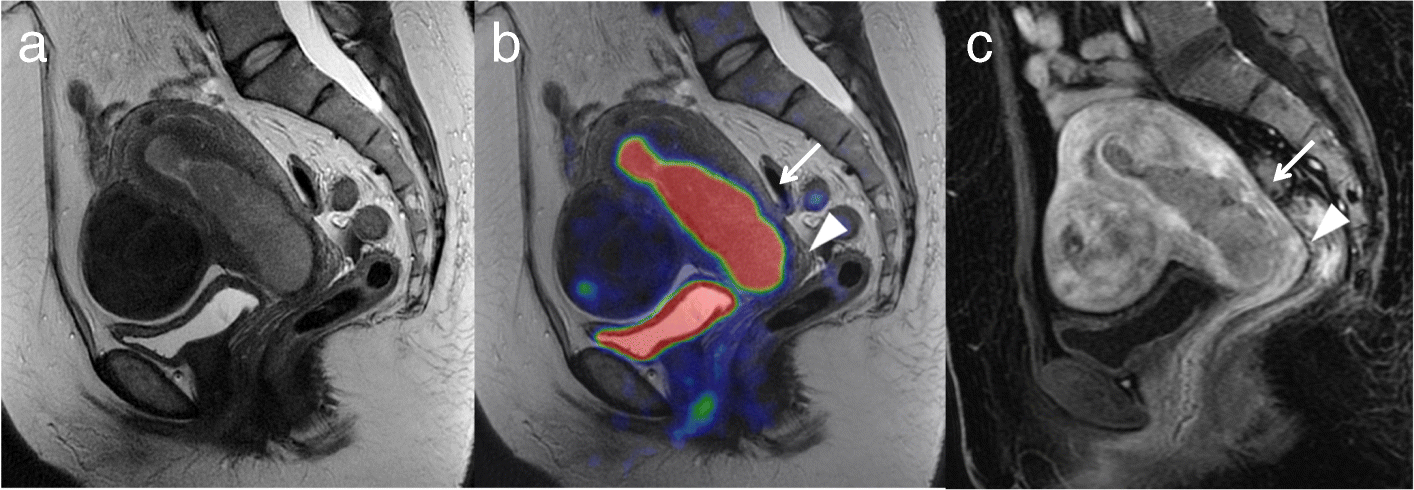

A 51-year-old woman with endometrial cancer invading 50% or more of the myometrium and cervical stroma (pT2). a. Sagittal T2-weighted MRI shows a large mass occupying the uterine cavity. b. Sagittal T2-weighted PET/MRI shows invasion of 50% or more of the myometrium (arrow) and cervical stroma (arrowhead). c. Sagittal T1-weighted dynamic contrast-enhanced MRI in the early phase shows the invasion of 50% or more of the myometrium without sub-endometrial enhancement (arrow) and cervical stroma (arrowhead). Histopathological examination of the surgical specimen was consistent with the imaging findings